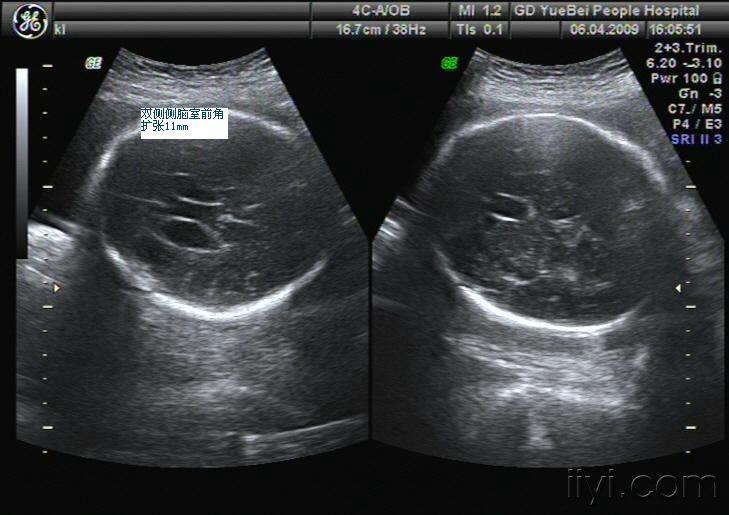

胎儿脑积水一例

脑积水的产前诊断

谁发一张4或5或6个月的胎儿脑积水的b超图片